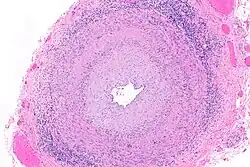

.jpg)

Przyczynami choroby są choroby zakaźne i autoimmunologiczne[2]. Zapalenie aorty w dużej części przypadków jest idiopatyczne[3][4].

Najczęstszymi nieinfekcyjnymi przyczynami zapalenia aorty są zapalenia dużych naczyń – olbrzymiokomórkowe zapalenie tętnic (subkliniczne zapalenie aorty występuje u 20-65% osób z rozpoznaniem) i choroba Takayasu[5][6][2][7][8][9][10]. Istotną przyczyną zapalenia aorty są czynniki infekcyjne. W 60% przypadków infekcyjnego zapalenia aorty przyczyną są Gram-dodatnie ziarniniaki: gronkowce, enterokoki i dwoinka zapalenia płuc[11]. Do przyczyn zapalenia aorty zalicza się[2][7][12][13][14][15]: